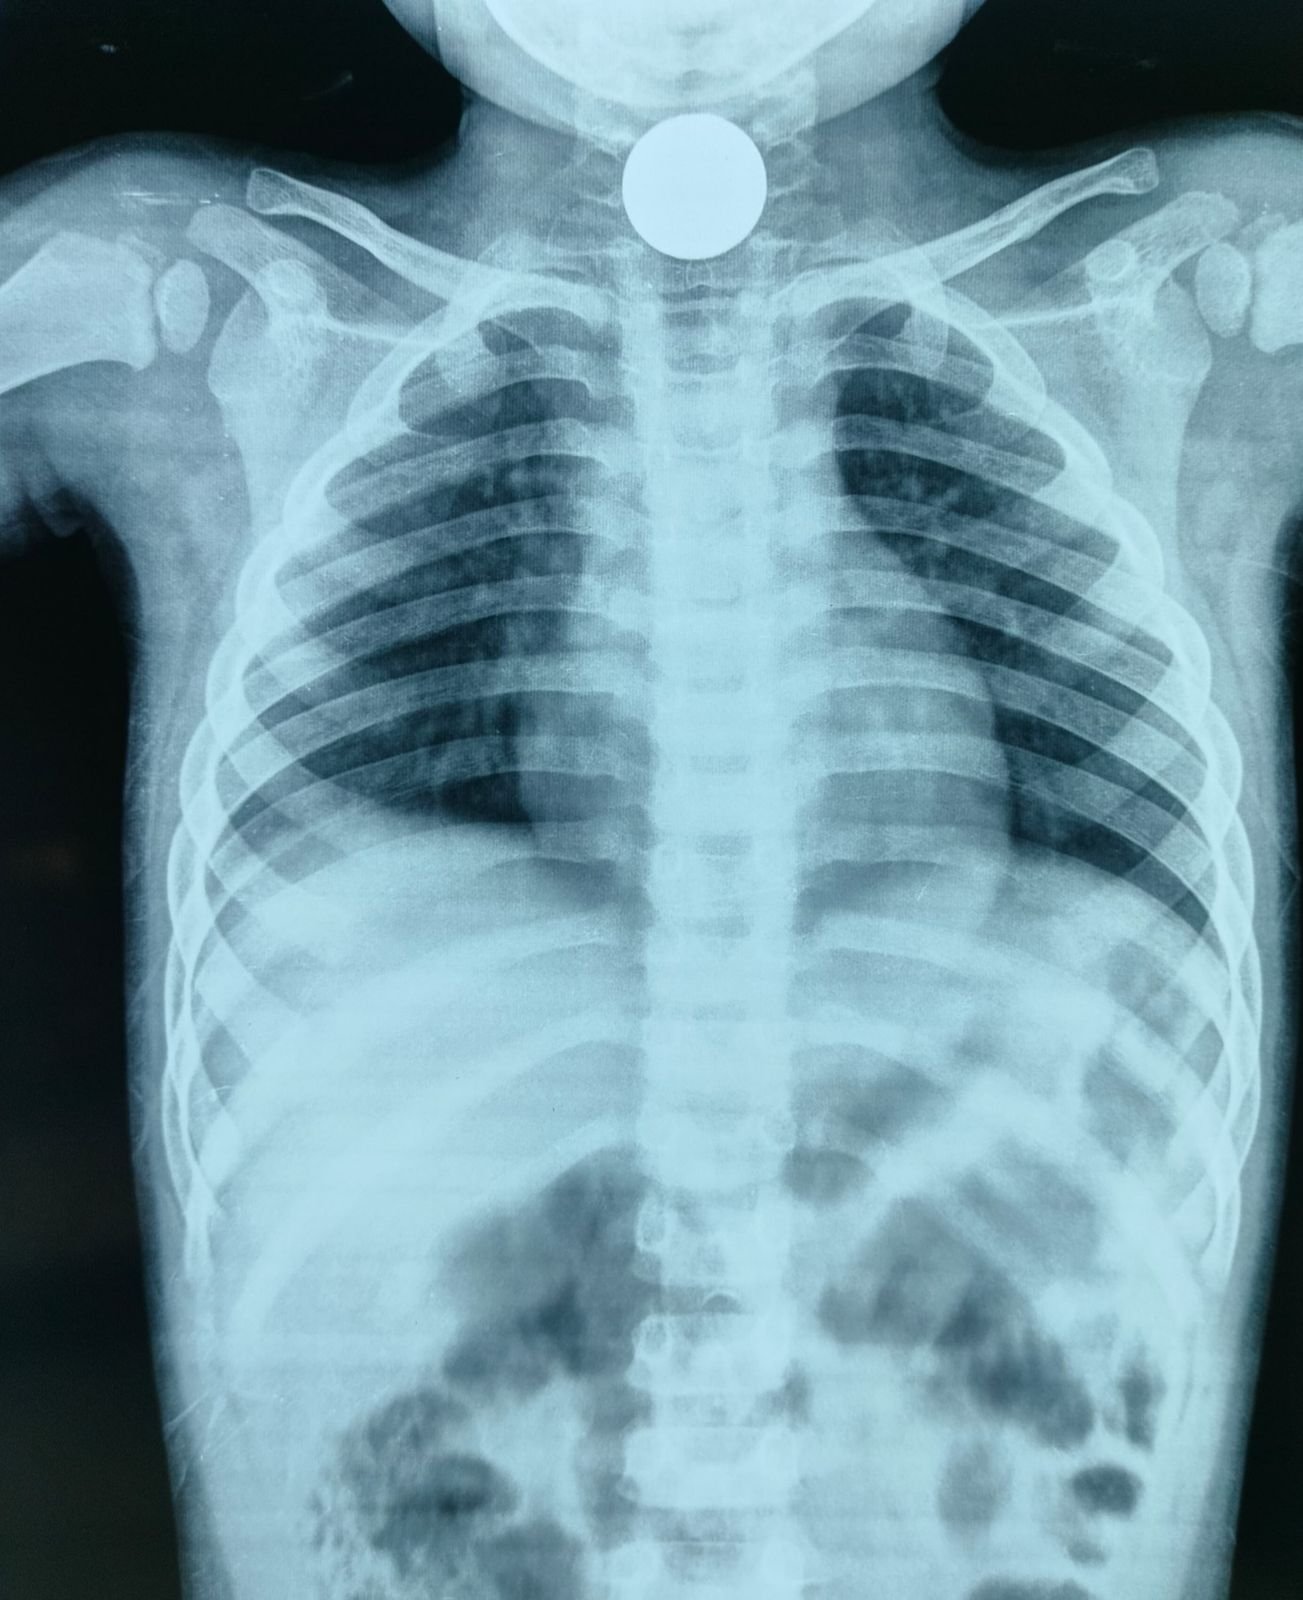

चम्पावत : शनिवार की सुबह चम्पावत के एक परिवार के लिए अचानक घबराहट और बेचैनी से भरी साबित हुई। खेलते-खेलते एक मासूम ने ऐसा कर दिया जिसकी किसी को उम्मीद नहीं थी — बच्चे ने गलती से एक सिक्का निगल लिया। बच्चे की साँसें उखड़ने लगीं, गले में तेज़ दर्द और घबराहट ने पूरे परिवार को झकझोर दिया। माता-पिता घबराए हुए तुरंत उसे लेकर जिला अस्पताल चम्पावत पहुंचे। अस्पताल पहुंचते ही डॉक्टर्स ने बिना समय गंवाए एक्सरे जांच की, और यह साफ़ हो गया कि सिक्का बच्चे के गले में अटक गया है।